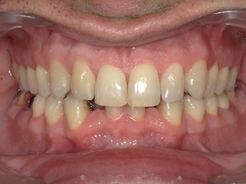

Présentation cas n°1 :

Présentation cas n°2 :